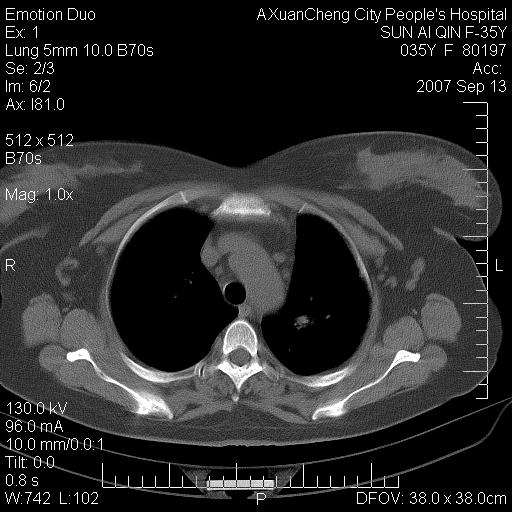

以下是引用天南地北在2007-9-13 13:43:00的发言:[br]考虑双肺、肺门侵润

以下是引用ydx_74在2007-9-13 15:42:00的发言:[br]仅看片,考虑右上肺癌并双肺转移,结合病史,考虑肺门、肺内淋巴侵润

以下是引用同在2007-9-13 15:08:00的发言:[br]支持肺门及双肺侵润.